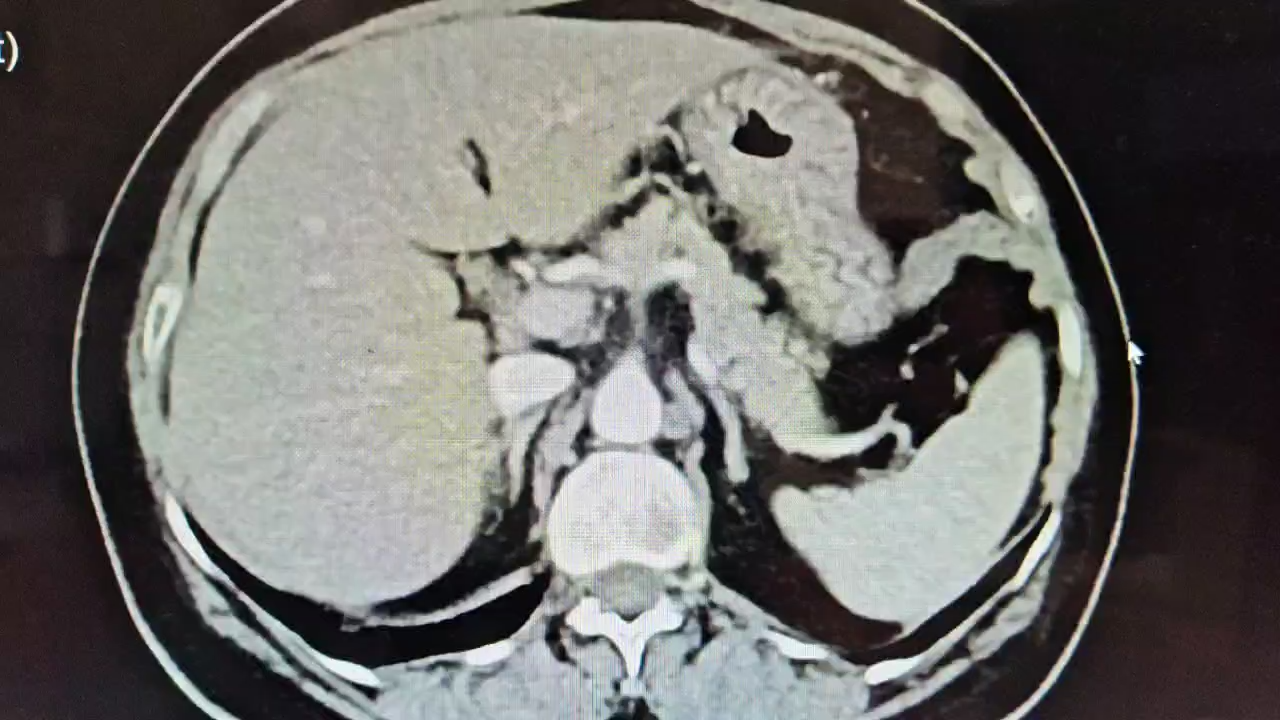

泌尿系CTU示:右肾下极占位,考虑肾透明细胞癌。

患者老年女性,右肾下极肿瘤体积较大及基底部较深,与肾门部血管及肾盂关系密切。根患者家属沟通后,行根治性切除术。